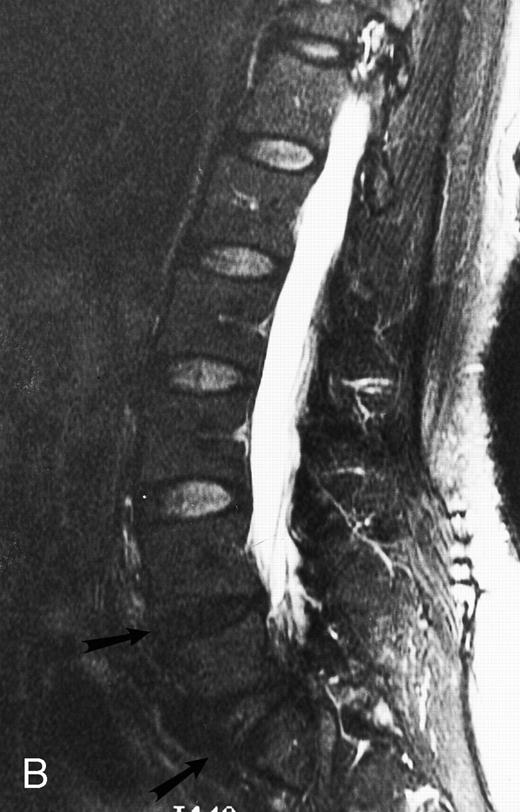

T1-weighted (500/11, TR/TE) sagittal MR images of the lumbosacral spine in a 45-year-old woman before (A) and 40 days after (B) bone marrow transplantation for multiple myeloma. There is a diffuse MR pattern of marrow involvement in (A) (bone marrow plasma cells, 50%; monoclonal protein, 6.0 g/dL). On the posttreatment image, there is definite reinstitution of fatty marrow in the spine and, in particular, around the basivertebral veins, in keeping with partial response to treatment (bone marrow plasma cells, 0.5%; monoclonal protein, 1.6 g/dL).